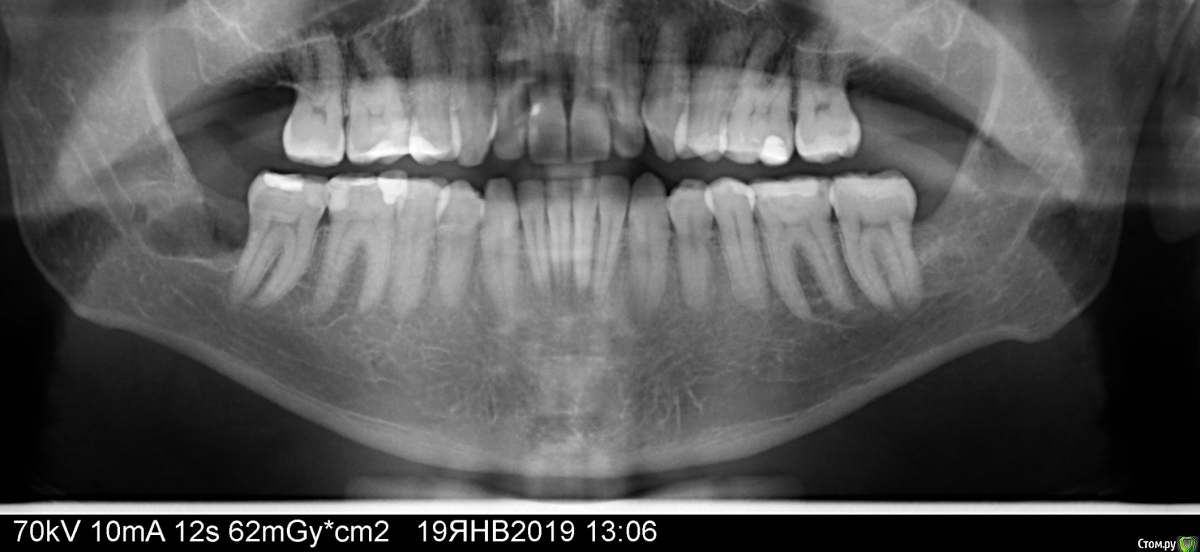

michaelks7 Опубликовано 21 января, 2019 Поделиться Опубликовано 21 января, 2019 (изменено) ЗдравствуйтеВот ситуация :14.01 удаляли нижнюю 8ку лежачая в кости полный комплектУдаление длилось около часа , травматичное . несмотря на мои просьбы обойтись без варварских методов, стоматолог и с помощью элеваторов итд смогла нанести значительный ущерб челюсти . Один раз даже ударила молотком - корень не выходил, отдельная тема для обсуждения почему она не использовала турбину для менее травматичного процесса . c предыдущим удалением зубов мудрости средней сложности я не могу придраться - быстро и восстановление минимально. по срокамНастоял на использовании PRF сгустка - взяли кровь из вены , заложили в полость , ушили и оставили дренажпрописали антибиотики/обезбаливающие / антигистаминныеПервые дня 3 стандартно каждые 5-6 часов билт челюсть отдает наверх и в ухо, обезбаливающие, небольшой отек , температуры нетПостепенно интервал между приемами увеличивается На 4-5й день происходит что-то странное - прием у хирурга - говорит все идет хорошо, убирает дренаж. в тот же день что-то дернуло меня набрать соленой воды для ванночки - не полоскания! - через пару секунд острая боль в области удаления и отдает в верхнюю челюсть проходит минут за 5, но после этого начинает ныть , эффект не сбивался полностью даже приемом кетанов . что странно ведь в тот день между обезбаливающими уже было 12 часов - прогресс по сравнению с первыми днями на след день 19.01 делаю панорамный снимок, помогло прикладывание к ранке марли с митрогилом - сильно уменьшило ноющие ощущения 20.01 на приеме своего у своего врача(стоматолога, не хирурга , она вроде как в другой больнице на дежурстве) она смотрит рану говорит вижу фибриновый сгусток, не вижу кровяной - обрабатывает лазером , закладывает коллапан с чем-то еще , говорит этого достаточно. ноющие ощущения остаются добавил 2 снимка - панорамный сделан 19 числа - причем даже я на нем вижу что частично сокет закрыт видимо фибриновым сгустком(логика))второй сделан летом на нем уже удаленный нижний зуб - близнец текущего(его снимка не нашел)Вот у меня и вопросы:это действительно альвеолит , при ушитой ране с закладыванием прф сгустка? реально ?кровяной сгусток должен образовываться и поверх фибринового или как в таких случаях проходит процесс?Вроде как прф и закладывается для более быстрого восстановления и профилактики подобных случаев Ну и вопрос что делать дальше? прием у хирурга во вторникP.s. должен отметить что болевой синдром уменьшается - с кетонала перешел на нурофен Изменено 21 января, 2019 пользователем michaelks7 Ссылка на комментарий

Дмитрий М Опубликовано 24 января, 2019 Поделиться Опубликовано 24 января, 2019 причем даже я на нем вижу что частично сокет закрыт видимо фибриновым сгустком(логика)) ???сгусток на снимке никогда не видно.на Рг снимок показывает только разность в плотности ткани. кость, зубы ближе к белому, мягкие ткани ближе к черному.сгусток либо есть, либо его нет. верочтно вы не верно пяняли своего доктора про фибрин )"ФИБРИН, нерастворимый волокнистый белок, необходимый для КОАГУЛЯЦИИ (сворачивания) крови. Фибрин образует наместе раны..." - такой белесоватый налет!и судя по снимкам, лунка полностью закрыта слизистым лоскутом.и если доктор Один раз даже ударила молотком это еще не означает травматичное удаление, а элеватор при удалении практически 100% используется, даже когда пилят турбинкой. и да, альвеолит может быть даже при использовании ПРФ , от этого никто не застрахован, уменьшается вероятность - да, но не исключает 4 Ссылка на комментарий